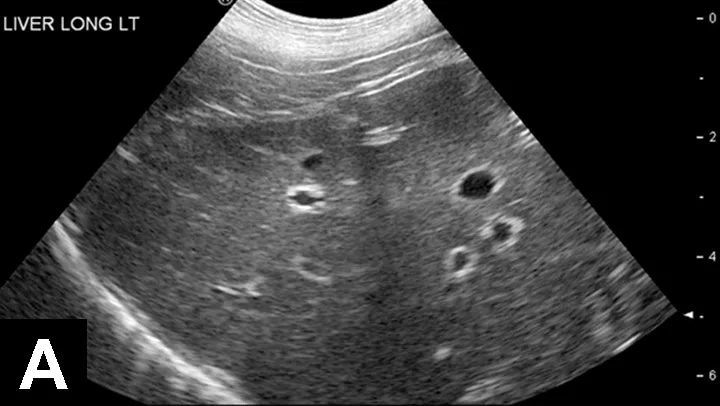

Figure 2A

Liver with normal parenchymal echogenicity in a dog (A); however, cytologic examination via fine-needle aspirate showed diffuse infiltration of malignant mast cells. Liver with normal ultrasonographic appearance in a cat (B); however, cytologic examination via fine-needle aspirate showed diffuse infiltration with lymphoblasts indicative of lymphoma.